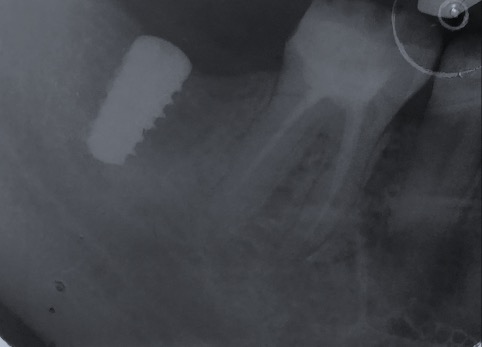

Un impianto dentale o fixture è un corpo in titanio, totalmente biocompatibile, che viene posizionato nella mascella o mandibola con lo scopo di sostituire la radice di un dente naturale perso. Su di esso viene successivamente o immediatamente quando possibile (carico immediato) fissata la protesi ovvero la corona del dente restituendo funzione ed estetica.

Gli impianti non hanno scadenza quindi non sono un rimedio temporaneo ma una soluzione definitiva per tornare ad avere denti come quelli originali. L’osteointegrazione è così forte e perfetta che se volessimo rimuovere l’impianto in un secondo momento dovremmo togliere anche l’osso che lo circonda.

Qualità degli impianti e tipo di trattamento di superficie, caratteristiche nel design della protesi e corretto posizionamento sono fattori fondamentali per ridurre il rischio di perdere un impianto.